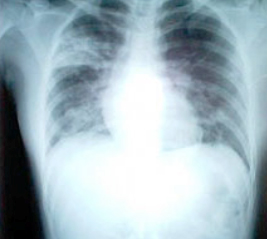

SARS患者患病十天的胸透照片

症状主要表现为:持续高烧(高于38℃),头痛和全身酸痛、乏力,干咳、少痰,部分病人有气促等呼吸困难症状,少数进展为呼吸窘迫综合征,肺部影像学显示肺炎改变。一般感冒病征包括发烧,咳嗽,头痛,可在数日后转好,并且一般没有肺炎迹象外周血白细胞计数无明显变化,淋巴细胞计数减少。抗菌药无效。SARS病毒能侵犯多种脏器,引起免疫系统对脏器的过度攻击,导致严重的脏器损伤。